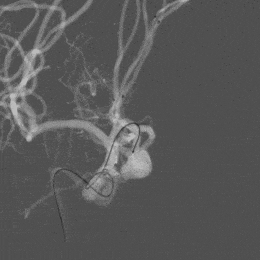

造影示“T”型支架左侧Atlas支架 3mm*15mm 、右侧 Atlas支架 4mm*21mm,动脉瘤致密栓塞,不显影。双侧A2段显影良好。

Atlas支架是低剖面,使用0.017"微导管输送。当栓塞系统需要三套同时在A1段内存在时,可以减少动脉管腔的血流阻碍效应。另外相比其他支架,需要0.021"甚至0.027"导管输送,在动脉瘤内成袢时有较低的动脉瘤壁压力,可以减少动脉瘤破裂出血可能性,减少灾难性结局的发生。